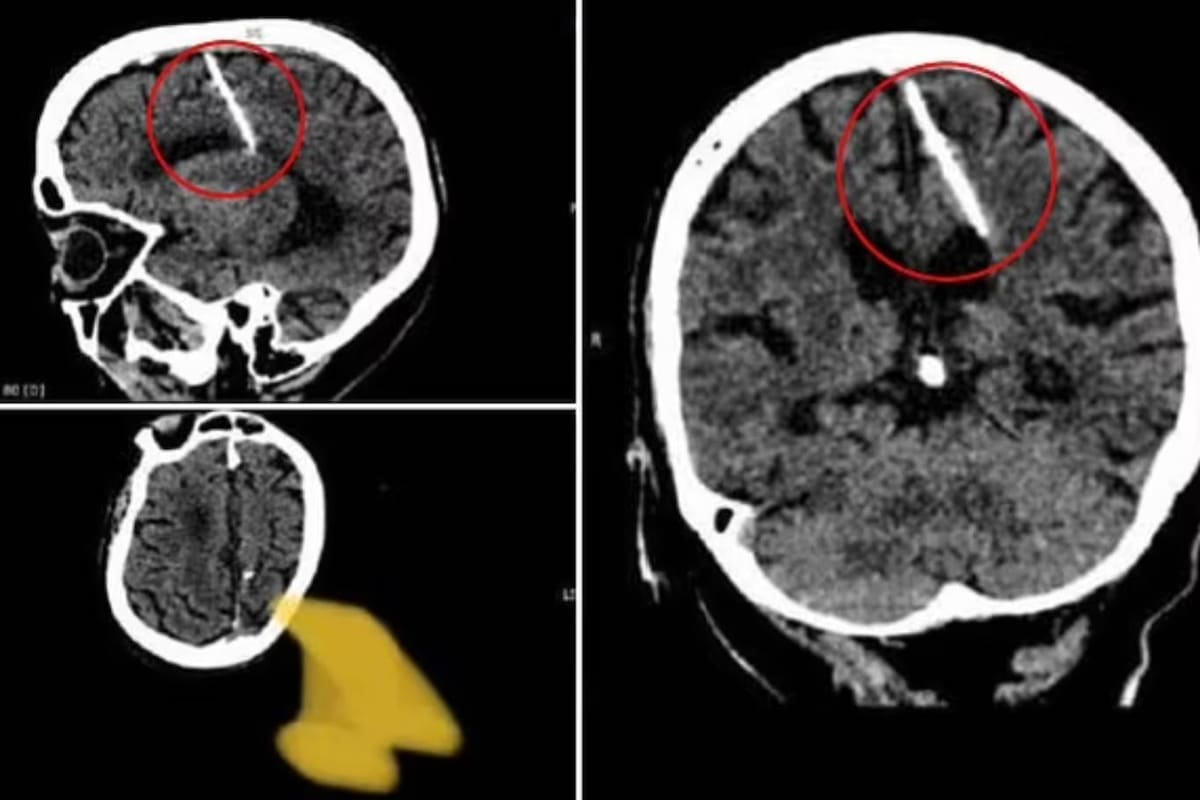

Una mujer de 80 años fue a un centro médico para hacerse una tomografía computarizada de su cerebro. Gracias a ese estudio, cuyo motivo no trascendió, tanto ella como los profesionales que la atendieron descubrieron con gran asombro que tenía insertada, en un sector de su lóbulo parietal izquierdo, una aguja de unos tres centímetros de longitud.

Como poco tiempo después la fontanela se solidificaba, el crimen de la bebé no dejaba pruebas y sus padres no recibían el castigo merecido por la muerte de la pequeña. Pero en este caso, según explica el Departamento de Salud de Sajalín, “la aguja penetró el lóbulo parietal izquierdo pero no tuvo el efecto deseado: la niña sobrevivió”.

Las autoridades de Salud de la isla aseguraron luego que la situación de la paciente no está en peligro con ese elemento instalado en su lóbulo parietal izquierdo, pero está siendo supervisada por personal especializado. El lóbulo parietal izquierdo, según informa el Daily Mail es el sector del cerebro donde se procesa la información sensorial y donde se desarrollan acciones complejas como las matemáticas.